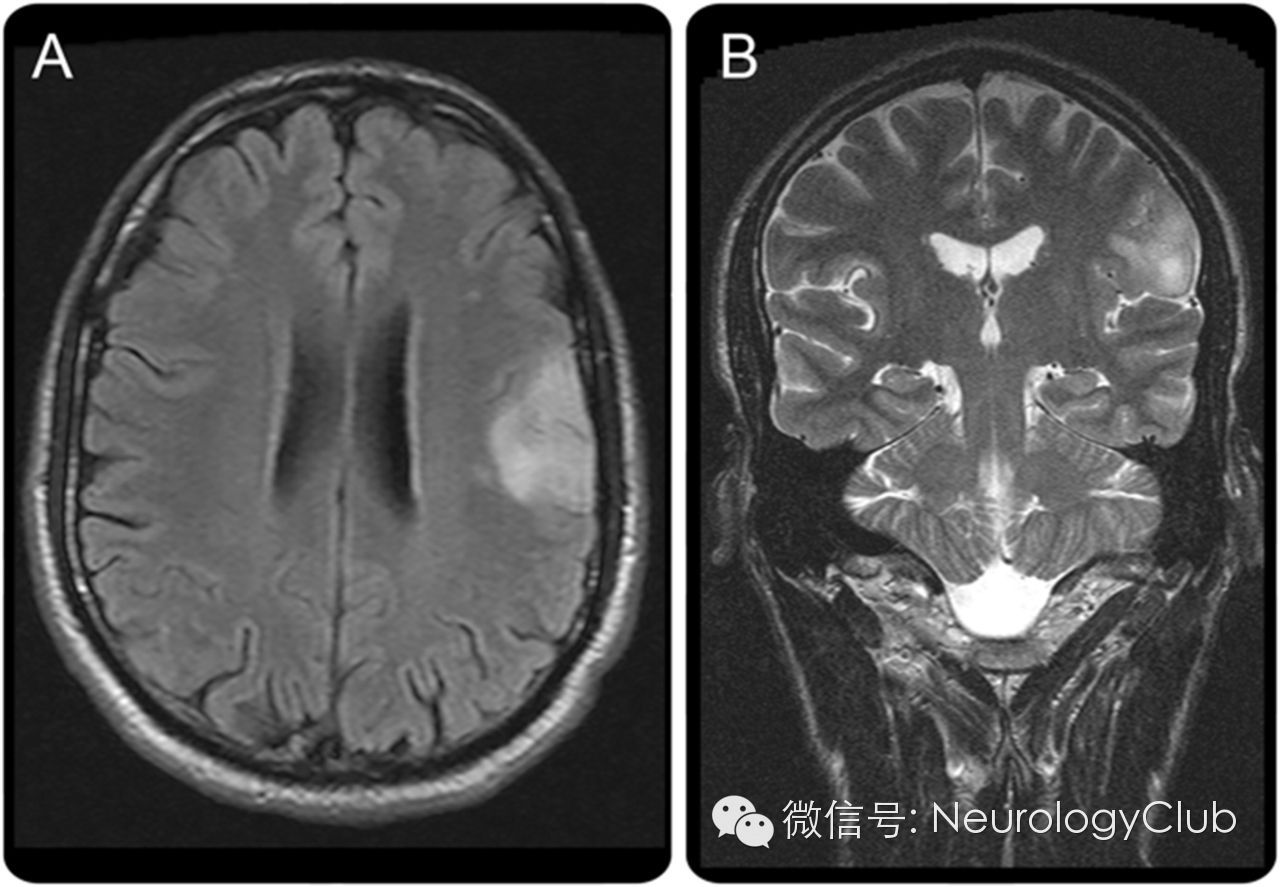

(图2 A:FLAIR上可见左侧岛盖部病灶;B:T2WI显示左侧岛盖病灶周围水肿)